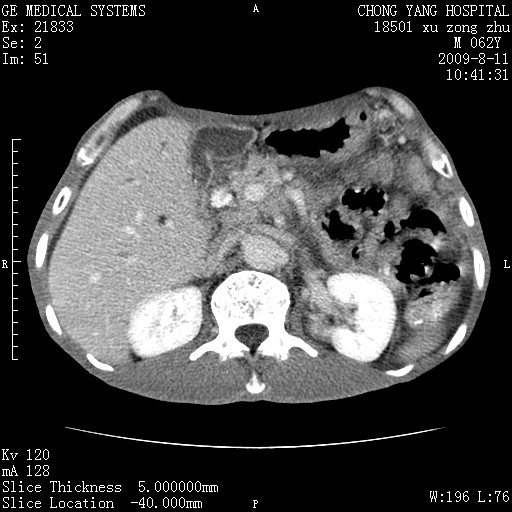

以下是引用杀毒软件在2009-8-11 16:35:00的发言:[br]肝内胆管扩张局限于左叶,胆管内有结石伴肝外胆管结石,胆管壁增厚呈弥漫性并发腹腔积液,胰腺边界模糊。[br][br]考虑---胆总管及肝内胆管结石继发胆管炎及胰腺炎,左肾下极囊肿,腹水。

以下是引用zjzjr在2009-8-11 17:35:00的发言:[br]肝内胆管扩张局限于左叶,胆管内有结石伴肝外胆管结石,胆管壁增厚呈弥漫性并发腹腔积液。[br][br]考虑---胆总管及肝内胆管结石继发胆管炎,左肾下极囊肿,腹水。